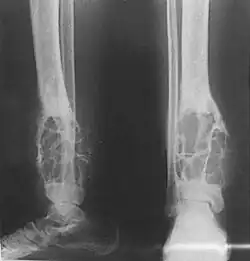

Patients typically present with swelling with or without pain. The slow-growing tumor predominantly arises in long bones in a subcortical location (95% in the tibia or fibula).[3]

Histologically, islands of epithelial cells are found in a fibrous stroma. The tumor is typically well-demarcated, osteolytic and eccentric, with cystic zones resembling soap bubbles.[2]

X-rays of the affected area show a well defined tumour in bone, with multiple lobules giving a "soap bubble" appearance.[9] MRI can provide a more useful guide to its severity.[9]